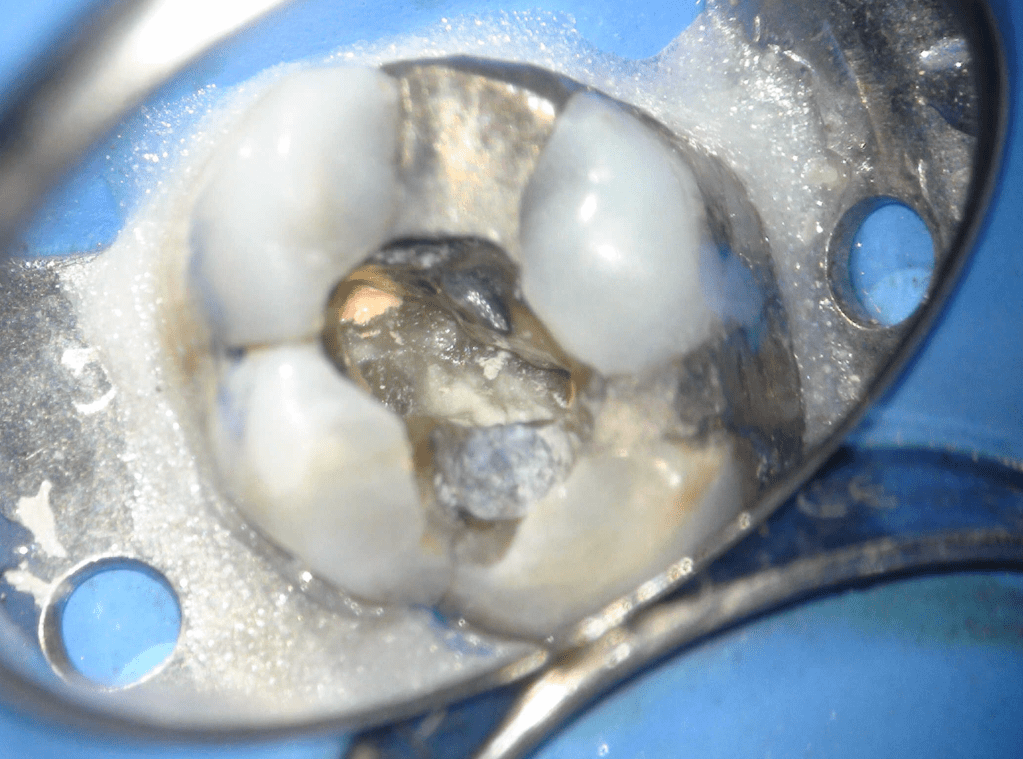

Fisura, remoción amalgama para explorar